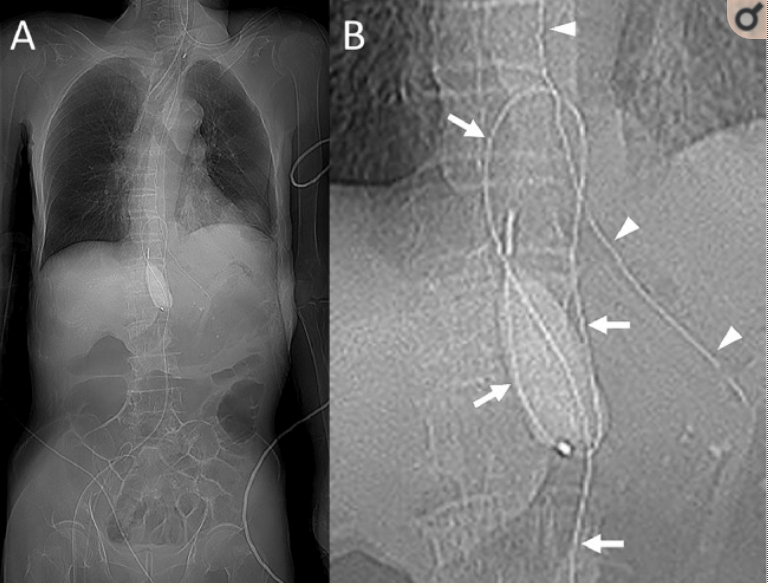

La tecnica REBOA consiste nell’introduzione per via percutanea di un catetere a palloncino nell’aorta, che viene gonfiato per ottenere una occlusione temporanea del vaso. In questo modo si ottiene:

Il REBOA è una tecnica salvavita che ha rivoluzionato la gestione delle emorragie non comprimibili, in particolare nei pazienti politraumatizzati in shock, nei casi selezionati di emorragia post-partum severa e, in contesti avanzati, anche nella gestione di arresto cardiaco non traumatico refrattario, come opzione per migliorare la perfusione durante RCP e aumentare i tassi di ROSC.